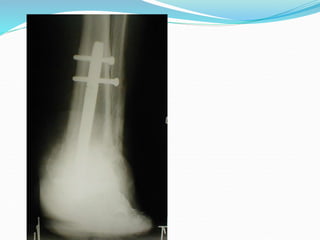

Case 3